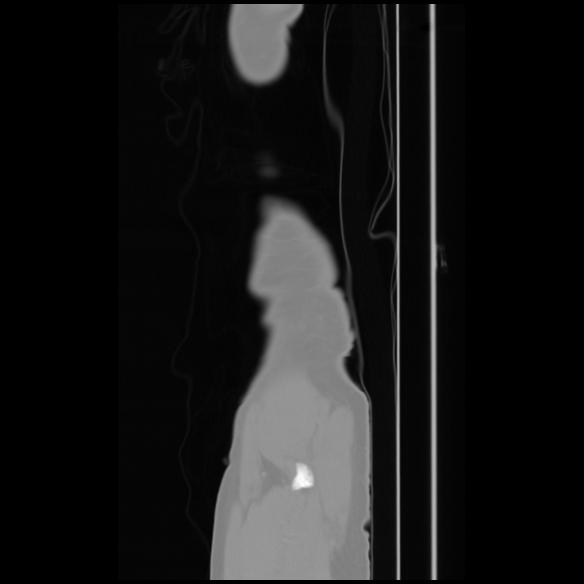

7 CUERPO,CE,Sagittal,3.000,CUERPO,Sagittal,